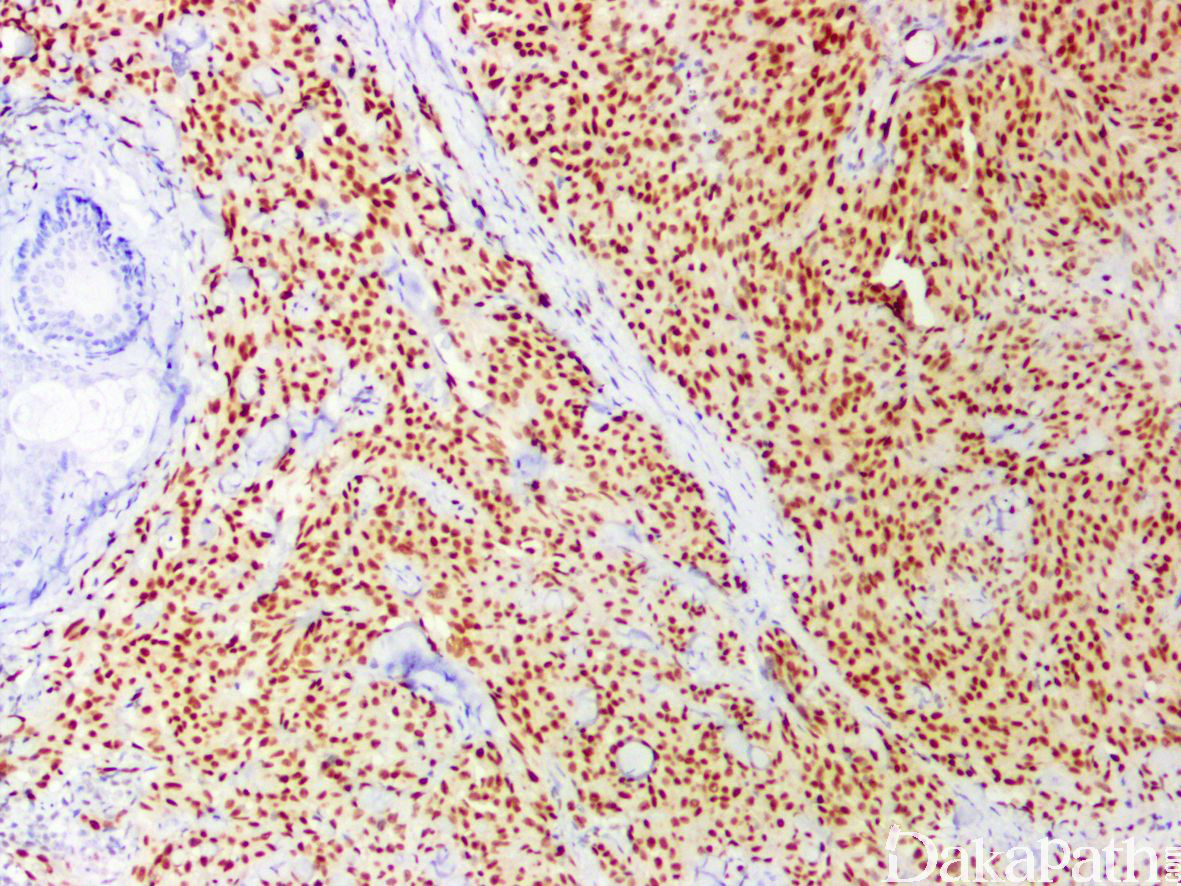

免疫组织化学染色:

CD31. CD34. FLI-1. ERG(+);约 1/3 病例表达细胞角蛋白,无 INI-1 表达缺失。